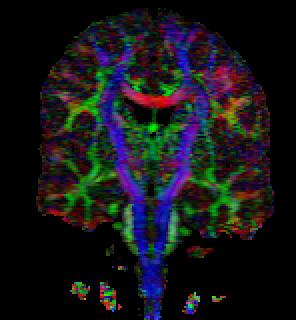

Tensor field of human brain visualization and tensor field interpolation